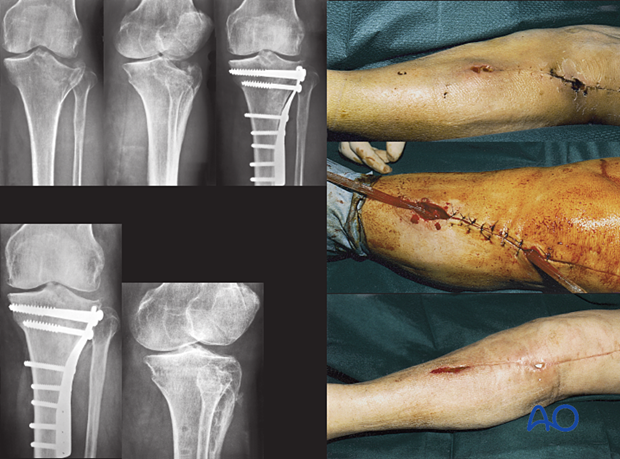

This Type A host had open reduction and internal fixation (ORIF) of her lateral plateau fracture. Healing was slow, and she returned with an open wound 24 days later. She immediately had aggressive debridement and antibiotics for two months. The wound and fracture then healed uneventfully.

The hardware was retained, but may have needed removal, or complete revision, if instability had been evident, or the infection failed to resolve.

Once the fracture was securely healed, the hardware was removed.